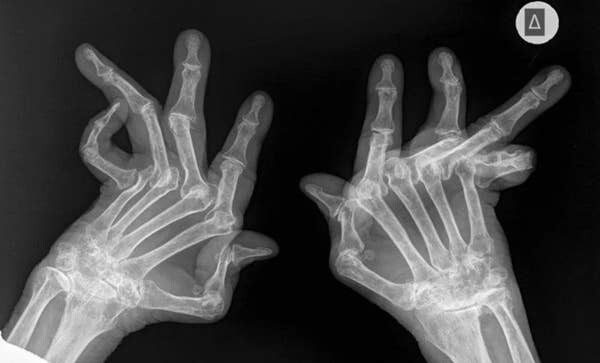

9. Ревматоидный артрит — это не шутки